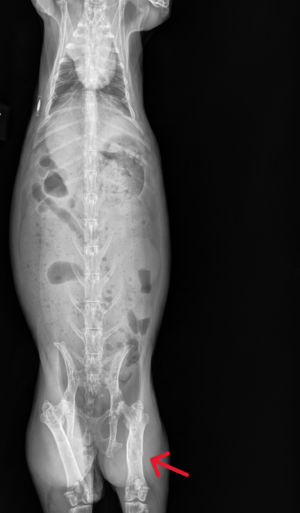

Osteosarcoma, or bone cancer, has been reported in domesticated rabbits. It is an uncommon cancer, diagnosed by x-ray imaging. Osteosarcoma is malignant and capable of metastasizing to other organs. The condition is characterized by hyperplasia and bone lysis. Affected bones will look perforated and misshapen on an x-ray due to the breaking down and overexpression of skeletal tissue.

This neoplasm can occur in various bones or joints, such as the glenohumeral joint, intertarsal joint, sacrococcygeal joint, and rib.